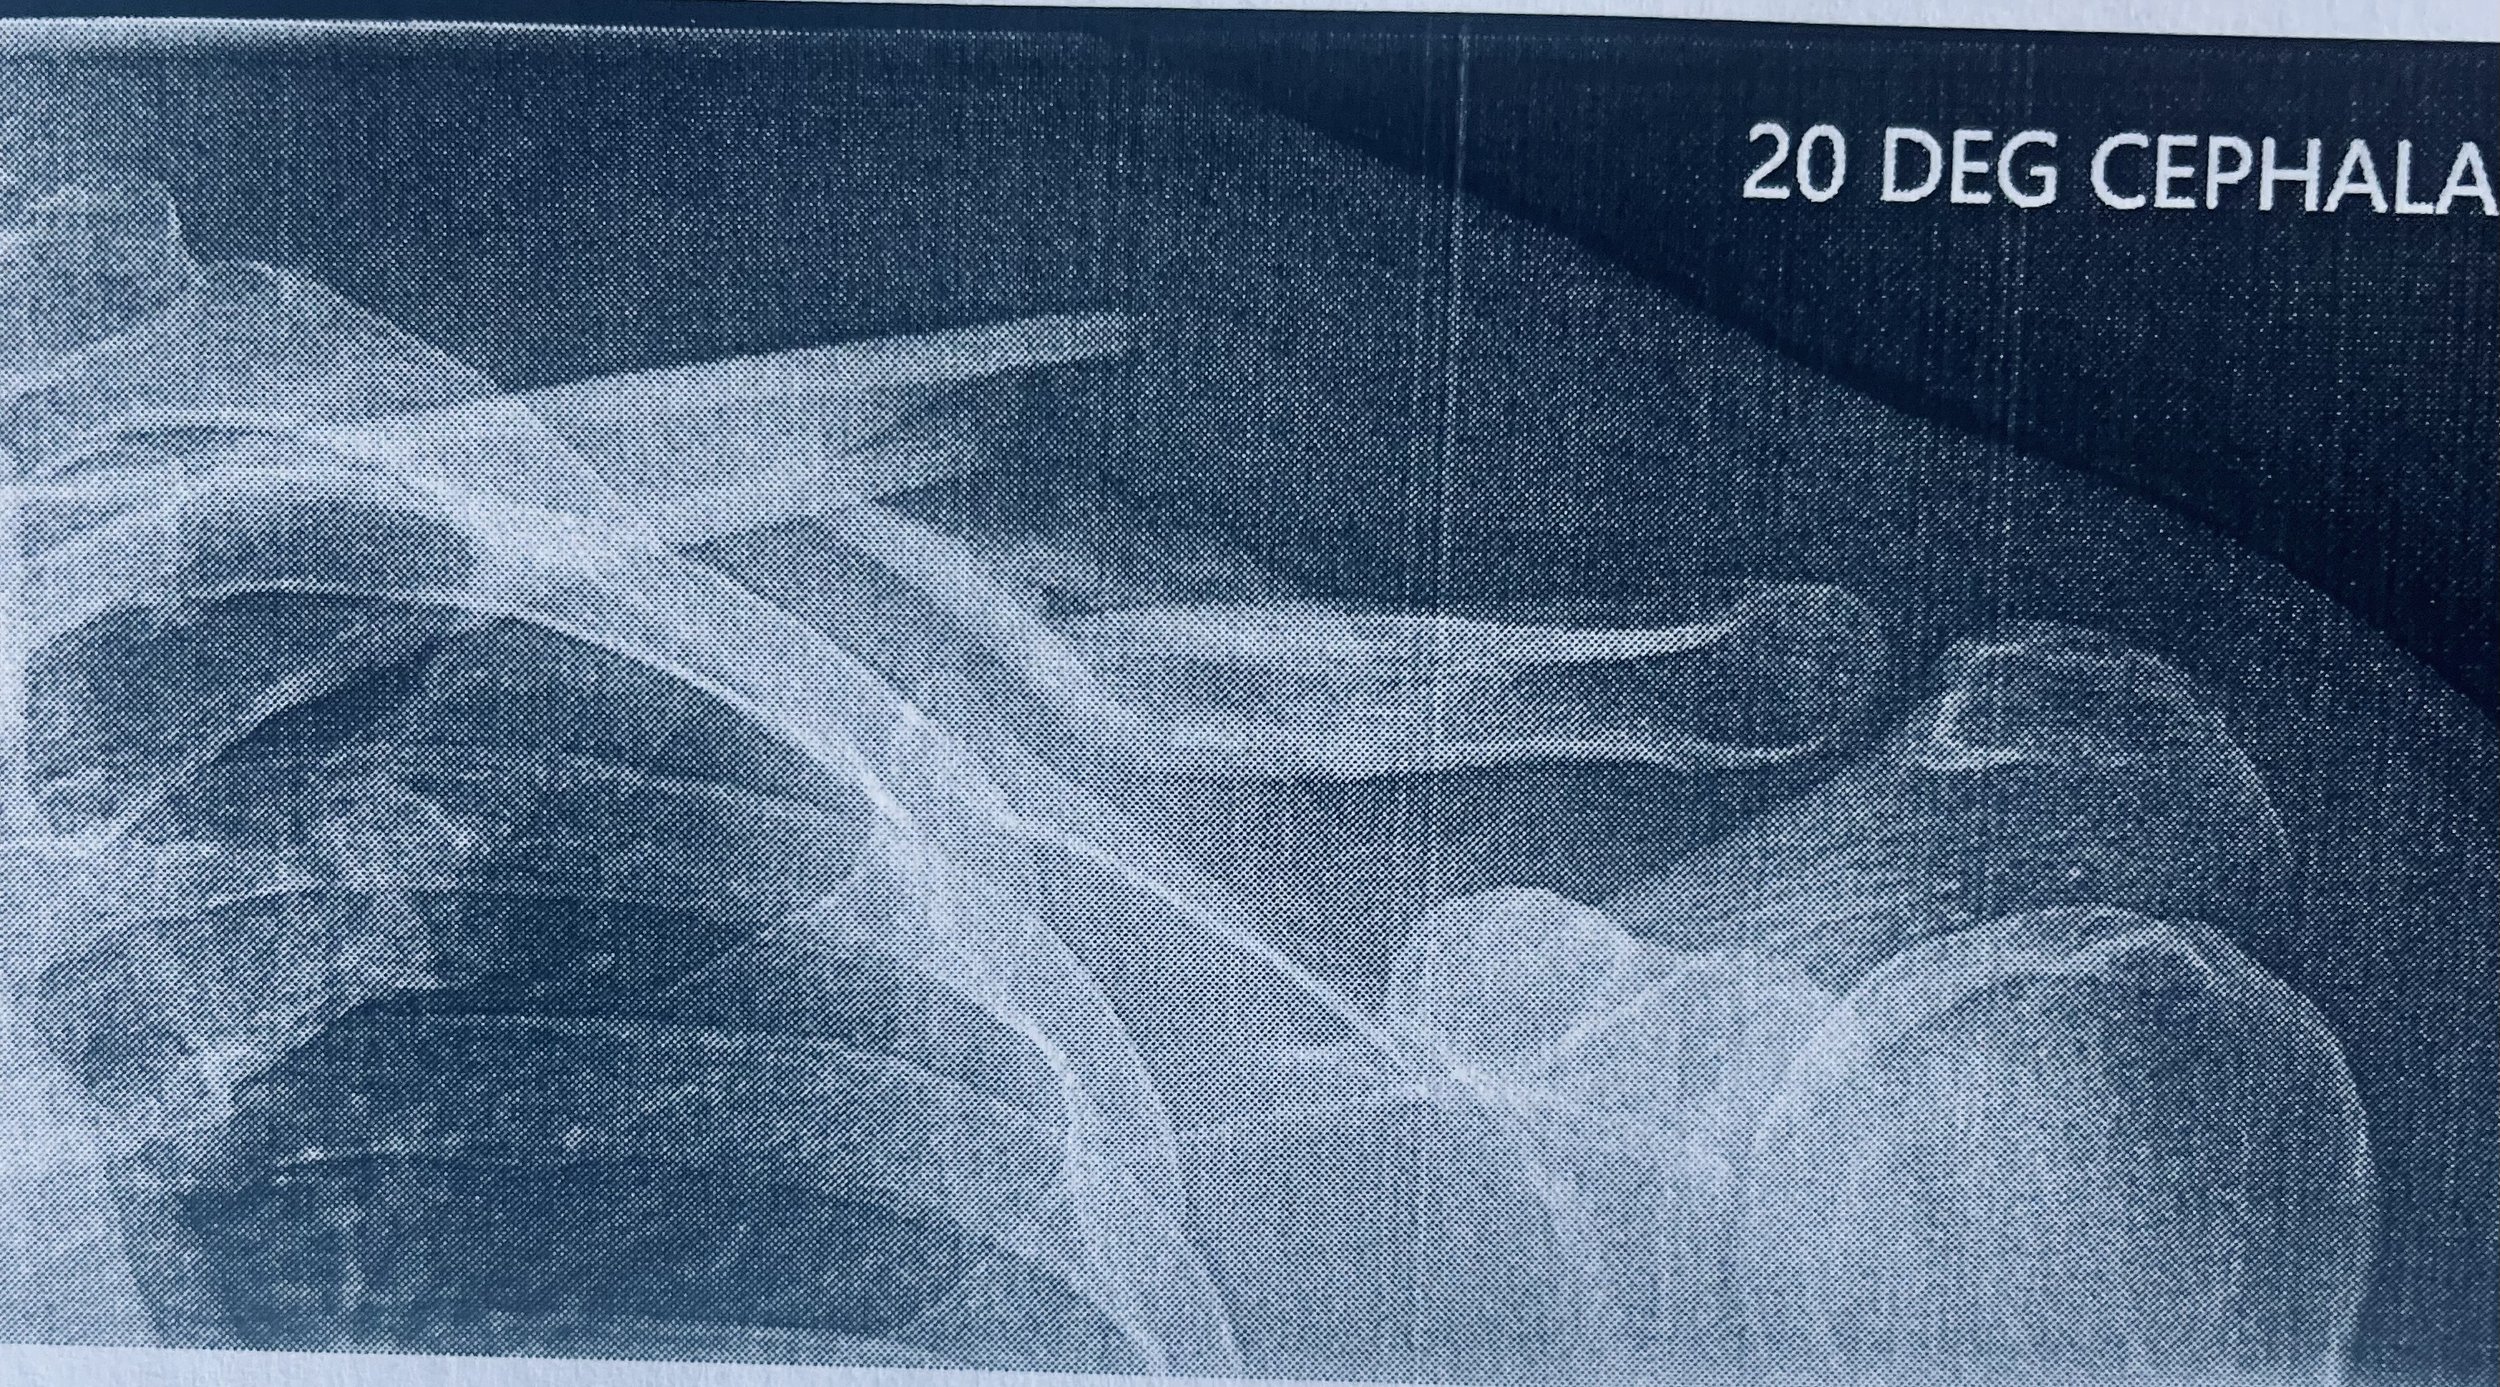

Your shoulder isn’t supposed to look like this, but mine did in July 2023. What kind of rescue insurance would I have wanted if this happened in the North Cascades? What if it had happened on the Matterhorn? What if it happened while I was riding a bicycle for fun the week before my Matterhorn trip? Here are my thoughts on the value of rescue and travel insurance.